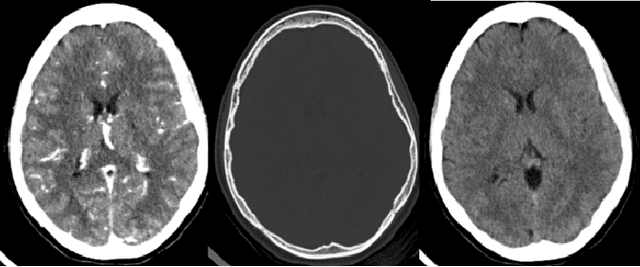

Abstract:Head CT is one of the most commonly performed imaging studied in the Emergency Department setting and Intracranial hemorrhage (ICH) is among the most critical and timesensitive findings to be detected on Head CT. We present BloodNet, a deep learning architecture designed for optimal triaging of Head CTs, with the goal of decreasing the time from CT acquisition to accurate ICH detection. The BloodNet architecture incorporates dependency between the otherwise independent tasks of segmentation and classification, achieving improved classification results. AUCs of 0.9493 and 0.9566 are reported on held out positive-enriched and randomly sampled sets comprised of over 1400 studies acquired from over 10 different hospitals. These results are comparable to previously reported results with smaller number of tagged studies.